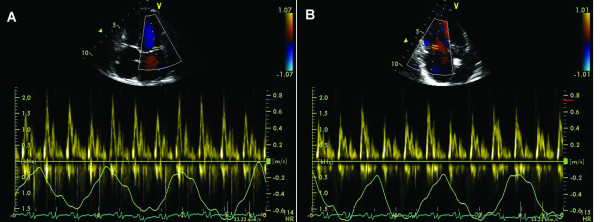

The Doppler images are suggestive of what cardiac pathology or condition?

Constrictive Pericarditis

Doppler findings for Constrictive pericarditis will show respiratory variations on the PW spectral doppler. The mitral valve velocity will increase with inspiration and decrease with expiration, while the tricuspid valve velocity will decrease with inspiration and increase with expiration.

False

Pericarditis versus Restrictive Cardiomyopathy: Select all the following answers (multiple answers) that apply to the image:

Surrounds entire heart, impedes diastolic filling

Restrictive/ Infiltrated Cardiomyopathy

Large MV E, small A, with respiratory changes

Involves infiltrated myocardium, stiff ventricular walls, impedes diastolic filling

Large MV E, small A, without respiratory changes

Pericarditis verses Restrictive Cardiomyopathy: Select all the following answers (multiple answers) that apply to the image: